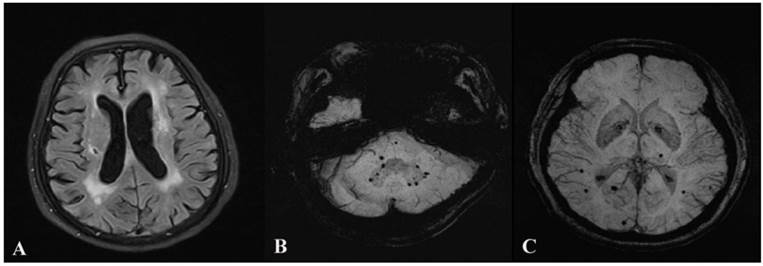

No statistical differences in age, sex, and vascular risk factors were found among the four groups. By contrast, significant differences in the scores in all four neuropsychological tests were found among four groups. Multiple comparisons of the four scales were further carried out among the groups. The results showed that the scores in all four tests were lower in the MB and MB&SBI groups than in the control group (all P<0.05), whereas only the scores in Clock Drawing Test and Verbal Fluency Test were lower in the SBI group than in the control group (both P<0.05). Multiple comparisons showed no statistical differences in the scores in all tests among the MB, SBI, and MB&SBI groups (all P>0.05). However, a downtrend can be observed from the control group to the MB&SBI group for all tests, and the scores in the four tests are the lowest in the MB&SBI group. The details are shown in Table 1. Examples of leukoaraiosis, silent brain infarctions and microbleeds were shown in Figure 1.

Fig 1

Advanced periventricular leukoaraiosis, silent brain infarction and microbleeds. Leukoaraiosis and silent brain infarction are shown on Image A. Lobar, deep and infratentorial microbleeds are shown on Image B and C.